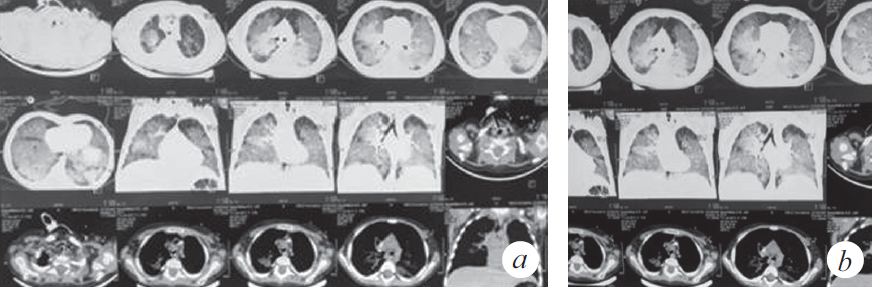

Через 2 нед. госпитализации в ОРИТ у ребенка наросли клинические и параклинические проявления госпитальной пневмонии (лихорадка, повышение С-реактивного белка до 39,7 мг/л), высев грибов рода Candida, Staphylococcus aureus — из верхних дыхательных путей; Еnterococcus faecalis, Еnterococcus fecuim, Klebsiella pneumoniae — из мочи, кала. На контрольной КТ: отрицательная динамика в виде увеличения консолидации в периферических отделах легких (рис. 2), клиническая картина не изменилась. На фоне антибактериальной терапии широкого спектра действия дыхательная недостаточность не прогрессировала, явления инфекционного токсикоза были купированы, кашель отсутствовал. Максимальная оценка по шкале SOFA (Sequential Organ Failure Assessment) 3 балла.

Рис. 2. Компьютерная томограмма органов грудной клетки (через 5 нед. от дебюта заболевания) (a). Признаки диффузного интерстициального повреждения легких. Отмечена отрицательная динамика в виде увеличения консолидации в периферических отделах легких (b)

Fig. 2. CT of the chest organs (5 weeks after the onset of the disease) (a). Signs of diffuse interstitial lung disease. Negative dynamics in the form of increased consolidation in the peripheral parts of the lungs (b)